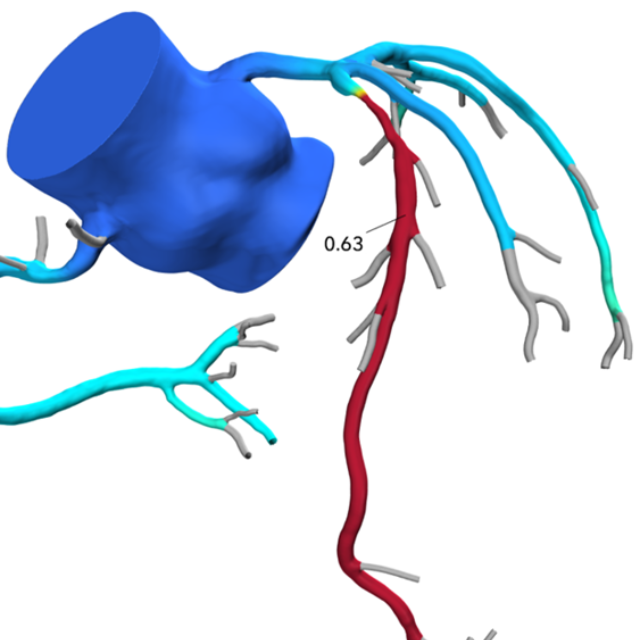

Beginning in 2026, interventional cardiology fellows will be offered formal training in coronary CTA, relying on structured CT reading sessions, lectures, and imaging case files to achieve Level II cardiac CT proficiency and qualification for the cardiac CT boards upon completion of interventional training. As our field shifts away from traditional stress imaging and towards coronary CTA as the preferred non-invasive method of assessment of CAD, there are emerging needs for interventional cardiologists to master coronary CTA for anatomic assessment of CAD, physiologic assessment with FFRCT and myocardium at-risk, morphologic assessment of plaque burden and characterization, and advanced planning of PCI for calcified plaque, bifurcation lesions, and CTO. Since ad-hoc PCI has become embedded in interventional practice, PCI planning with CTA allows precise equipment selection; reduces procedural time and radiation exposure to the patient and staff; allows the best opportunity for risk assessment for the patient and family, even before the patient goes to the cardiac catheterization laboratory. The Interventional Cardiology Fellowship Program at William Beaumont University Hospital is the first to offer formal cardiac CT training as part of its curriculum.